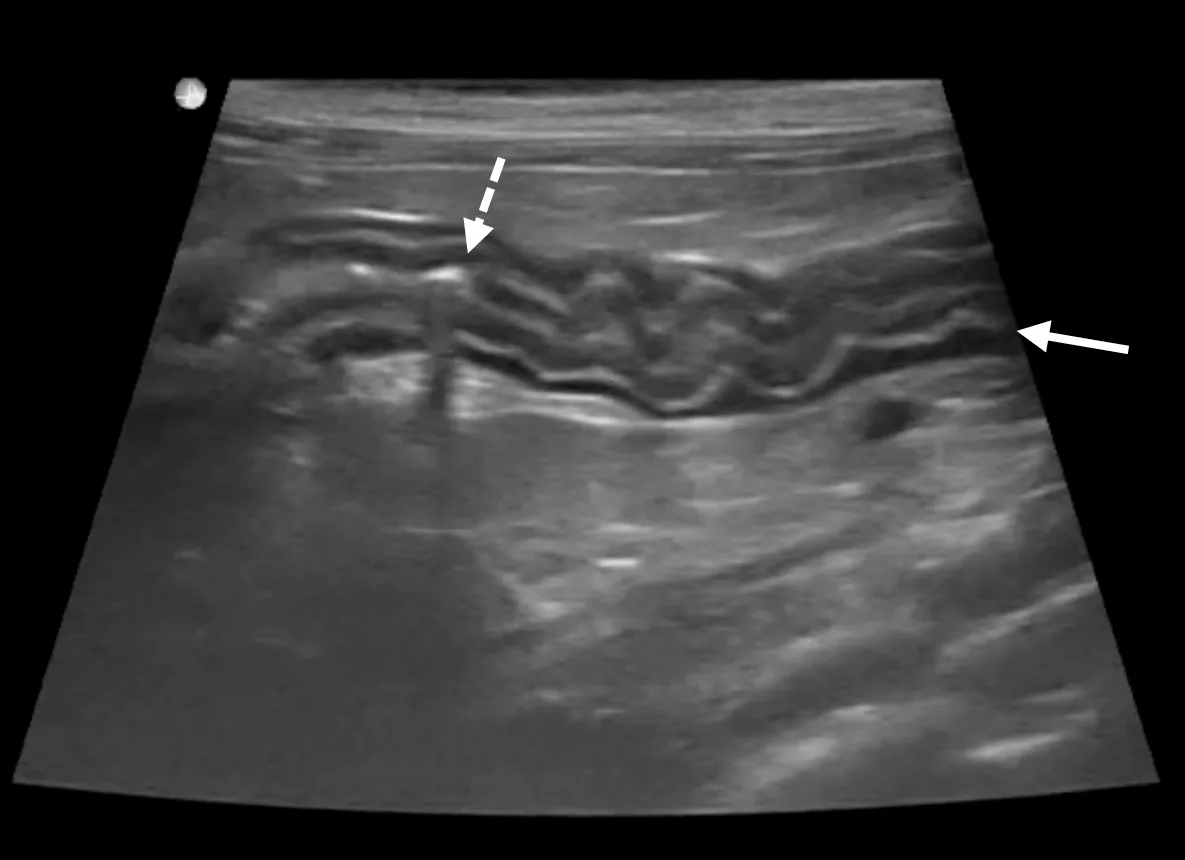

Radiography is nonspecific, and radiographs may appear normal. Ultrasonographic findings may include thickening of the general bowel wall or muscularis layer (Figure 1), mucosal changes, and mesenteric lymphadenopathy; however, ultrasonography is not sensitive or specific for IBD, and results may be normal.19,20

Ultrasound of the duodenum in a cat showing mild generalized muscularis layer thickening (arrow). The corrugated appearance and increased gas within the lumen (dashed arrow) support spastic hypermotility consistent with duodenitis, assuming an upper GI linear foreign body has been excluded.